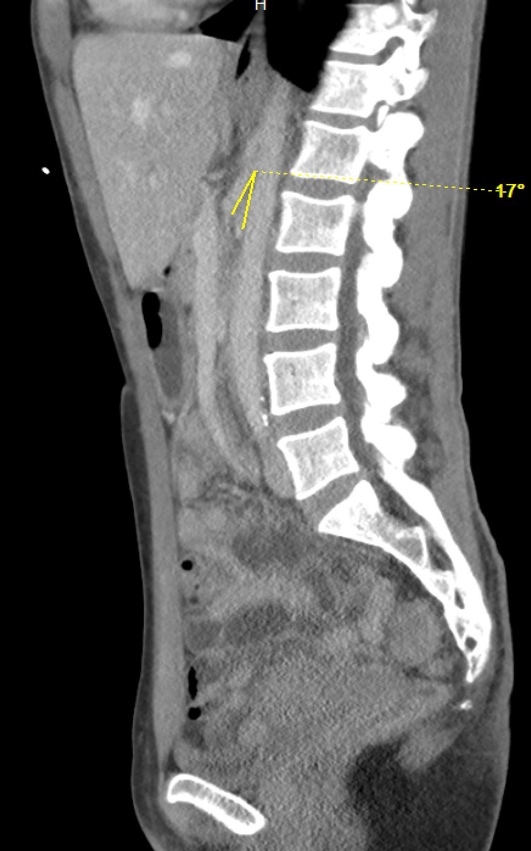

On hospital Day 1, an esophagogastroduodenoscopy (EGD) with nasogastric tube placement was completed with removal of approximately two liters of chyme (i.e., acidic gastric fluid). Initial computer tomography was reviewed by Radiology, and SMAS was diagnosed (Images 1 and 2). After a multidisciplinary review consisting of the case’s internal medicine, gastroenterology and general surgery teams, the patient was transferred to a tertiary care center where a gastrostomy-jejunostomy tube was placed. She was started on tube feedings and reported improvement of symptoms at follow-up one month later.

Pertinent findings on physical exam included mid-epigastric abdominal pain with an underweight BMI of 18.6. Computer tomography of the abdomen and pelvis with intravenous contrast provided a radiological diagnosis of SMAS (Images 3 and 4).